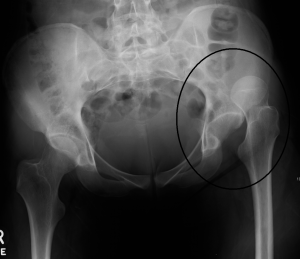

Диагностика как правило осуществляется при рентгенологическом исследовании. Вывих бедра относится к экстренной травматологии, кроме выраженной боли смещение головки бедра может сопровождаться сдавливанием сосудов и нервов, что может сказаться на жизнеспособности ноги.